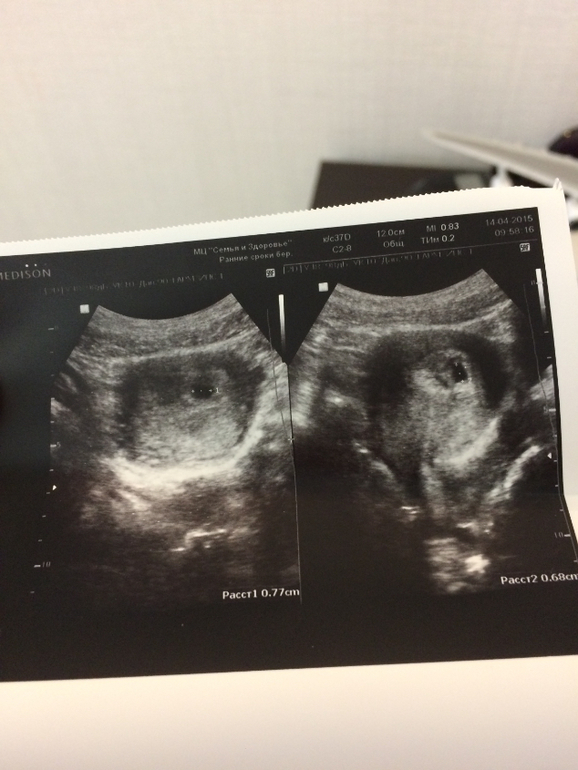

Я беременна уже 100 проц; узи подтвердило плодное яйцо в матки; срок 3-4 недели!!! Очень рада!!!